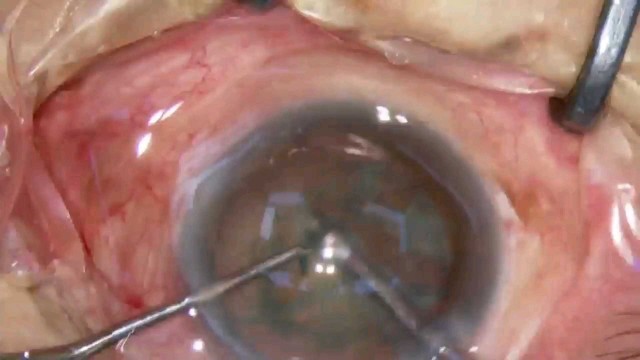

号外号外,湖南省人民医院副院长祖雄兵和眼科主任医师曾琦被指存在不正当关系,并有不雅视频传出。对此,医院工作人员回应:组织正在调查,请给医院宣传部门联系。当地卫生健康委员会对此回应:暂未接到相关的信访反映。祖雄兵为湖南省人民医院副院长,泌尿外科学科带头人。曾琦,博士,主任医师,硕士研究生导师。现任湖南省人民医院眼科副主任、眼科一病区主任,湖南省卫生健康高层次青年骨干人才,湖南省预防医学会眼病防治专业委员会主任委员、湖南省女医师协会眼科专业委员会主任委员、湖南省医学会眼科学专业委员会防盲学组副组长、湖南省医学会眼科学专业委员会眼外伤及职业病学组副组长、湖南省医学会眼科学专业委员会白内障学组副组长、